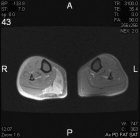

B.S. - 47 year old female with one year history of right knee pain, pain is posterior and is worse with activity, some relief with NSAID's